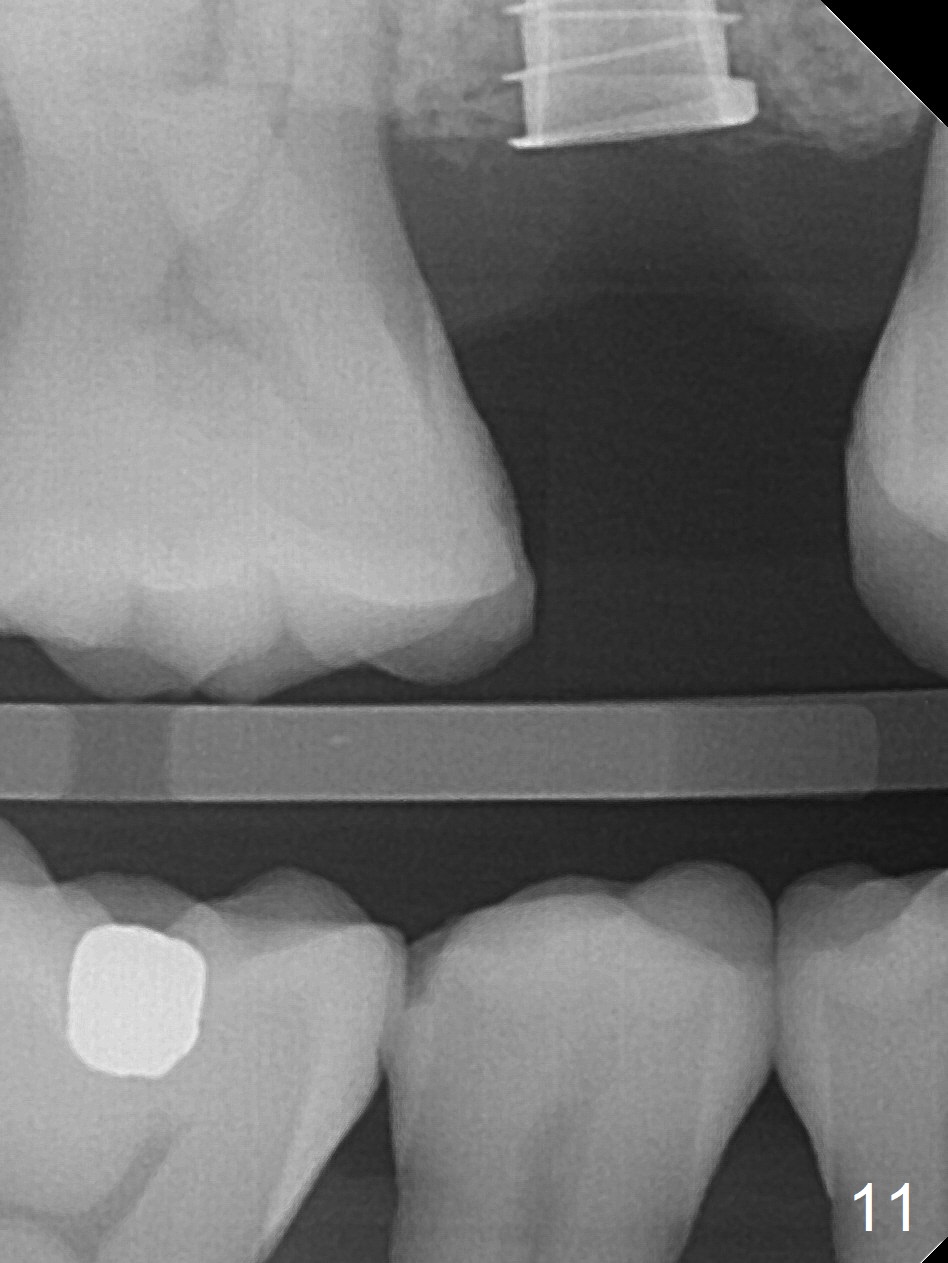

A 47-year-old man returns emergently with subgingival fracture of the lingual (L) cusp of the tooth #4 (Fig.1-3). After extraction (no bony defect) without drilling, a 4x11 mm dummy implant is placed as a tap drill with satisfactory stability (Fig.4,5). To get subcrestal placement, a shorter (4x9 mm) implant is inserted with insertion torque of < 35 Ncm. In retrospect, a larger implant (4.5 mm) would be better in term of primary stability. After allograft placement into the buccal and lingual gaps, a 4.5x4(4) mm abutment is placed for an immediate provisional. There is a peri-implant gap 7 months postop (Fig.7<, as compared to the implant at #2 (6 months postop)) . When the loose abutment is being retightened, the patient feels pain, although the gingiva appears healthy (Fig.8). A larger implant should have been used; the abutment should have been removed. The implant dislodges while the abutment is untightened 8 months postop. The osteotomy is found intact. A 4.5x11 mm dummy implant is placed 2 mm subgingival with 20 Ncm (Fig.9). When a 4.5x11 mm definitive implant is placed 3 mm subgingival (Fig.10,11), torque reaches 50 Ncm. A 5.5x3 mm healing abutment is placed. Three months postop, the implant is stable (Fig.12,13) and impression is taken.